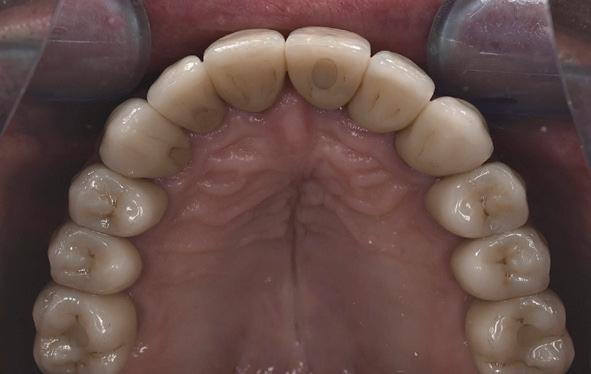

plaatsing van de restauraties werden zowel de tandboog als de tandstand in de bovenkaak gecorrigeerd (afbeelding 13-15).

Aansluitend werd de onderkaak volgens hetzelfde principe gerehabiliteerd, resulterend in een stabiele, functionele en esthetisch gebalanceerde occlusie (afbeelding 16-17).

male prothetische uitkomst. Tijdens de restauratieve fase speelde de restauratief behandelaar een actieve, dirigerende rol door continu het ontwerp bij te sturen in nauwe samenwerking met het tandtechnisch laboratorium. Door regelmatige evaluatiemomenten, zoals na vervaardiging van de mock-up, werd de prothetische planning verfijnd. Tevens vond er intensieve gedeelde besluitvorming plaats tussen restauratief behandelaar en patiënt, waardoor individuele wensen optimaal werden geïntegreerd in het definitieve behandelresultaat.

Ook de rol van de patiënt is hierin van doorslaggevend belang. In dit geval toonde de patiënt een hoge mate van motivatie en betrokkenheid. Hij verbeterde zijn mondhygiëne aanzienlijk en bleef gedurende het gehele behandeltraject therapietrouw en besluitvaardig. Zonder deze actieve medewerking was het bereikte resultaat niet mogelijk geweest. Het eindresultaat leidde tot merkbare tevredenheid bij de patiënt, die na afronding van de behandeling aangaf zich zichtbaar en voelbaar tien jaar jonger

te voelen (afbeelding 18) Een uitspraak die treffend weerspiegelt wat bereikt kan worden wanneer visie, interdisciplinaire samenwerking en patiëntbetrokkenheid samenkomen.